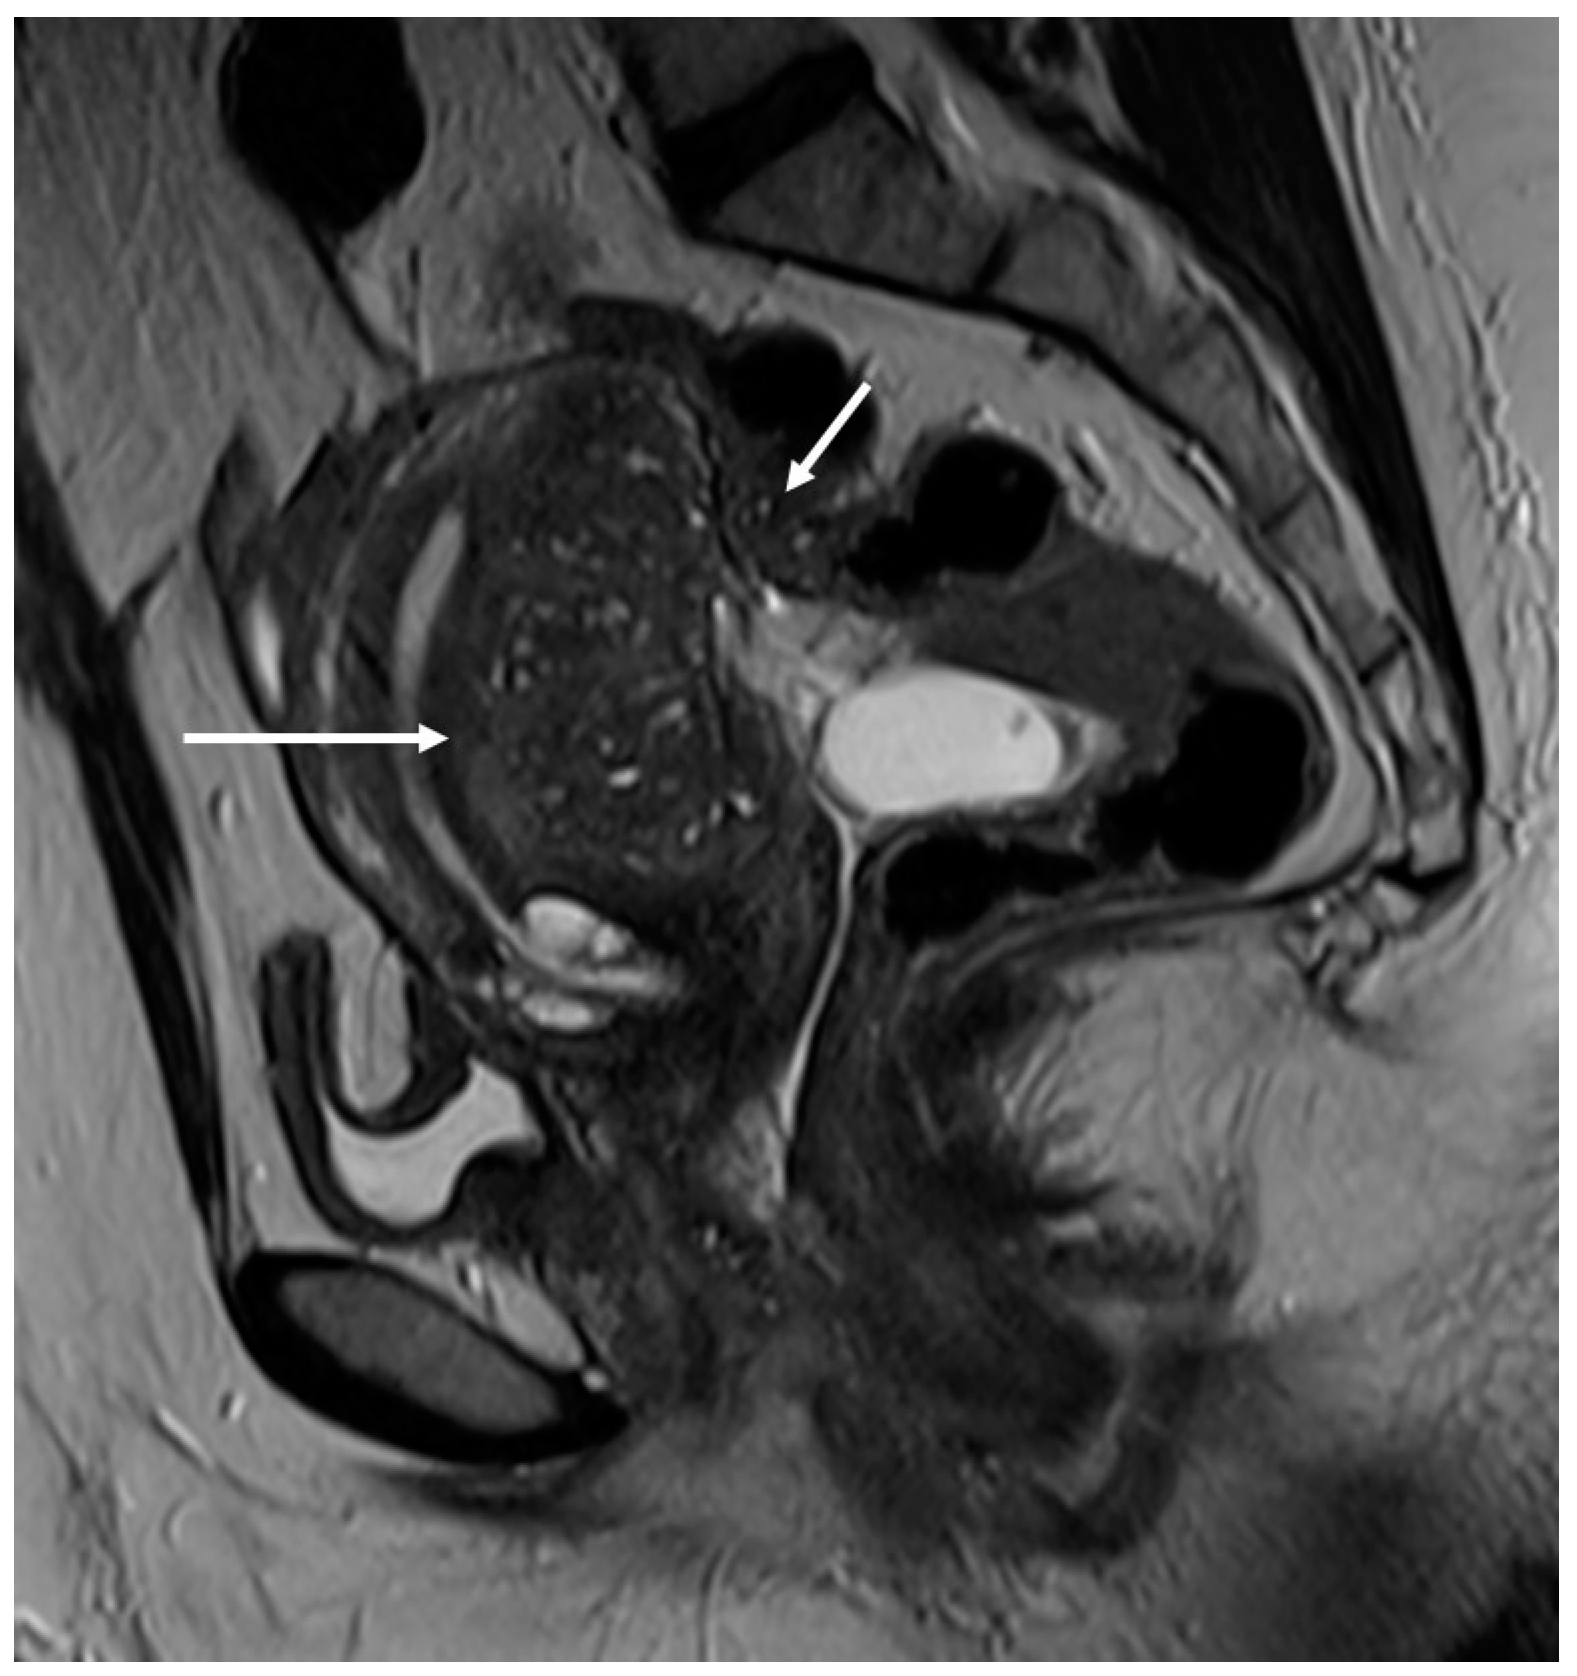

6.4. Neural Involvement

- Rousset, P.; Florin, M.; Bharwani, N.; Touboul, C.; Monroc, M.; Golfier, F.; Nougaret, S.; Thomassin-Naggara, I.; ENDOVALIRM Group. Deep Pelvic Infiltrating Endometriosis: MRI Consensus Lexicon and Compartment-Based Approach from the ENDOVALIRM Group. Diagn. Interv. Imaging 2023, 104, 95–112. [Google Scholar] [CrossRef]

- Chamié, L.P.; Ribeiro, D.M.F.R.; Tiferes, D.A.; de Macedo Neto, A.C.; Serafini, P.C. Atypical Sites of Deeply Infiltrative Endometriosis: Clinical Characteristics and Imaging Findings. Radiographics 2018, 38, 309–328. [Google Scholar] [CrossRef]

- Tang, X.; Ling, R.; Gong, J.; Mei, D.; Luo, Y.; Li, M.; Xu, J.; Ma, L. Deep Infiltrating Endometriosis MR Imaging with Surgical Correlation. Quant. Imaging Med. Surg. 2018, 8, 187–195. [Google Scholar] [CrossRef] [PubMed]